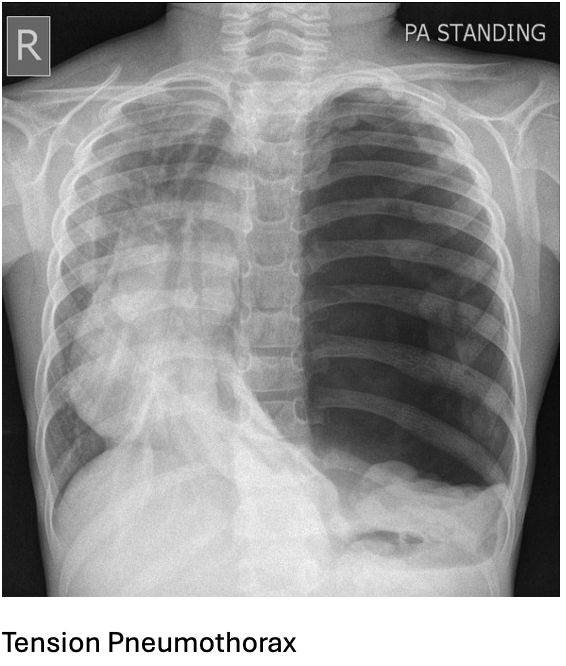

Answer: B) Tension pneumothorax – Needle decompression

Explanation:

This 35-year-old male presents with chest trauma and signs of respiratory distress, including decreased breath sounds on the left side, tracheal deviation to the right, and distended jugular veins. These clinical signs suggest a tension pneumothorax, a life-threatening condition where air is trapped in the pleural space, increasing pressure, and causing a shift of mediastinal structures (such as the trachea) to the opposite side. The immediate intervention for tension pneumothorax is needle decompression to relieve the pressure and prevent further deterioration.

Option A is incorrect because although an open pneumothorax (also known as a sucking chest wound) can cause similar symptoms, it is not characterised by tracheal deviation or distended jugular veins. The immediate treatment for open pneumothorax would be to apply a chest seal to prevent air from entering the pleural space.

Option C is incorrect because while a massive haemothorax (large amount of blood in the pleural cavity) can cause similar respiratory distress and decreased breath sounds, the key finding in this case is the tracheal deviation and distended jugular veins, which are more typical of tension pneumothorax. The immediate treatment for haemothorax is the insertion of a chest tube.

Option D is incorrect because flail chest (multiple rib fractures leading to a segment of the chest wall moving independently) can cause respiratory distress, but it does not typically cause tracheal deviation or distended jugular veins. The treatment for flail chest is to provide pain management, support ventilation & secure ribs using metal plates.

Option E is incorrect because cardiac tamponade (fluid accumulation in the pericardial sac) can cause distended jugular veins and respiratory distress, but it would not typically present with tracheal deviation to the opposite side of the fluid accumulation. The treatment for tamponade is pericardiocentesis, but the patient’s presentation is more consistent with a tension pneumothorax.